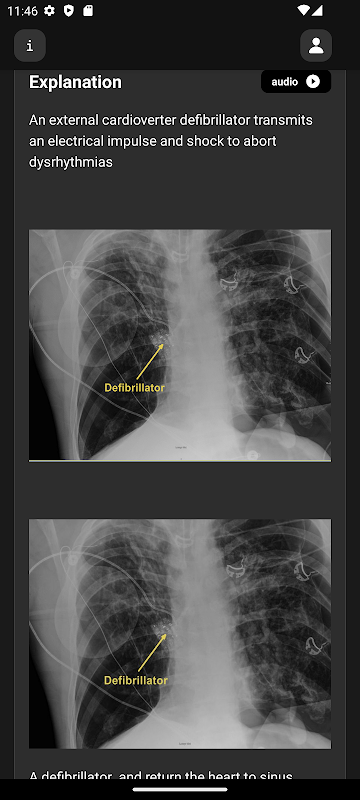

Immagini radiologiche, video e animazioni di alta qualità